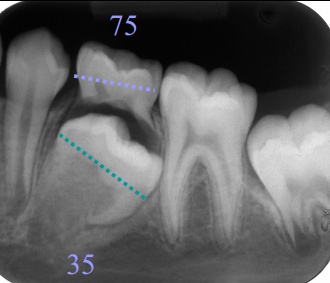

Define fusion

Fusion of 2 teeth --\> reduced number of teeth on the arch. Important to examine radiographically to reveal extent of fusion and decide on management

36

4 forms of fusion

* One large tooth * Bifid crowns with one root * 2 teeth united by dentin * Rarely, 2 teeth united by enamel